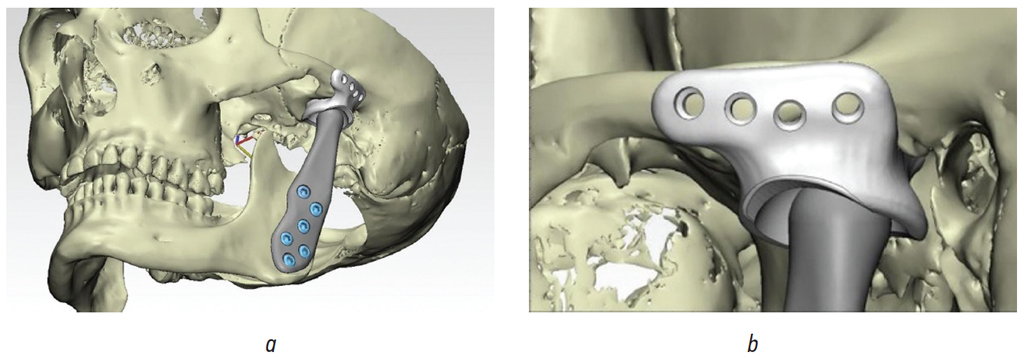

Обоим пациентам предложен аппаратурно-хирургический план лечения, подразумевающий санацию полости рта, декомпенсацию соотношения зубных рядов при помощи брекет-системы, двучелюстную/одночелюстную операцию с перемещением обеих челюстей/нижней челюсти вперед. Анализ КЛКТ височно-нижнечелюстного сустава (ВНЧС) пациента Ч. (рис. 8 а, b) позволил рассматривать в качестве альтернативного плана коррекцию соотношения зубных рядов в сагиттальном и вертикальном направлениях при помощи аппарата Гербста [2–4]. Анализ КЛКТ ВНЧС пациентки Ж. (рис. 9 а, b) выявил переднее положение головки нижней челюсти справа и ее резорбцию слева, что позволило обосновать план лечения с применением ортогнатической операции и эндопротезированием с целью коррекции признаков ЗЧЛА в сагиттальном, вертикальном и трансверзальном направлениях [5] (рис. 10).

Рис. 10. Титановый эндопротез височно-нижнечелюстного сустава: общий вид в черепе (а), фиксация искусственной суставной ямки к скуловой дуге (b) (данные из архива П.Н. Вопиловского, А.В. Павлова, Д.М. Ельчанинова)

Fig. 10. Titanium endoprosthesis of the temporomandibular joint: general view in the skull (a), fixation of the artificial articular fossa to the zygomatic arch (b) (data from the archive of P.N. Vopilovsky, A.V. Pavlov, D.M. Yelchaninov)